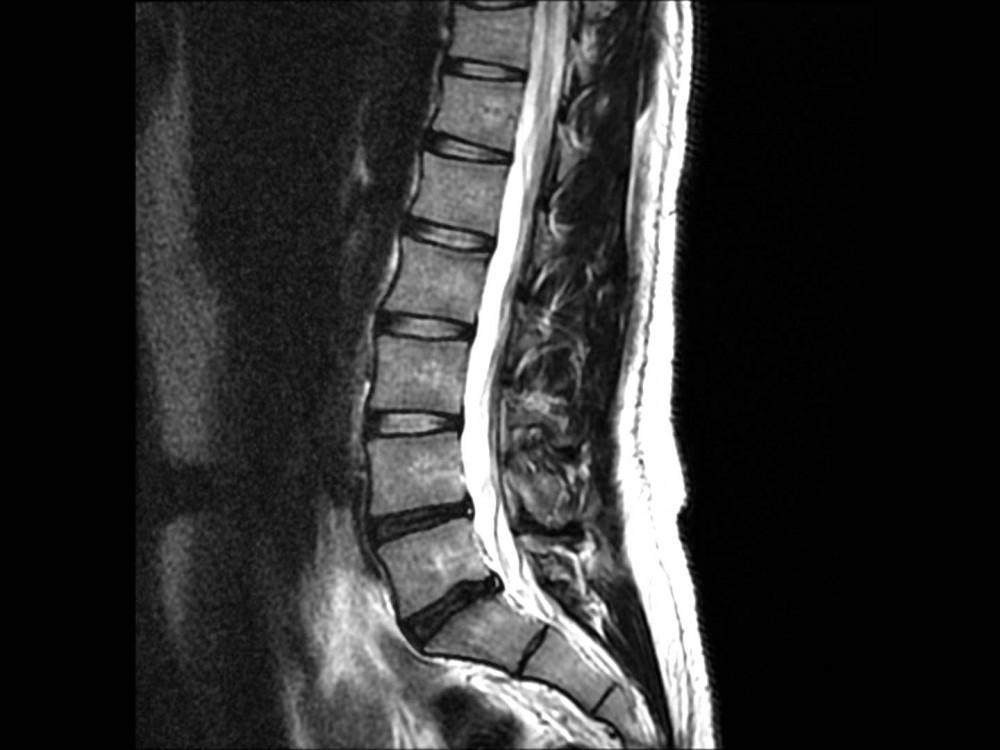

Even though MRI(magnetic resonance imaging) is considered a “gold standard” in evaluating spinal problems it is not perfect. The difficulty with the results of an MRI scan, as with many other diagnostic studies, is that the “abnormality” that shows up on the MRI scan may not actually be the cause of back pain. Numerous clinical studies have shown that approximately 30% of individuals in their thirties and forties have a lumbar disc herniation on their MRI scan, although they do not have any back pain.

We do see abnormal MRI findings in patients with no symptoms; in one of the published studies the prevalence of herniated disk was as high as 22% to 36% while study subjects had absolutely no complaints. The opposite is true as well and patients can have spinal pain with normal or inconclusive MRI findings. In this case further worked-up with additional tests including specialized X-ray studies and/or diagnostic nerve blocks would be indicated.